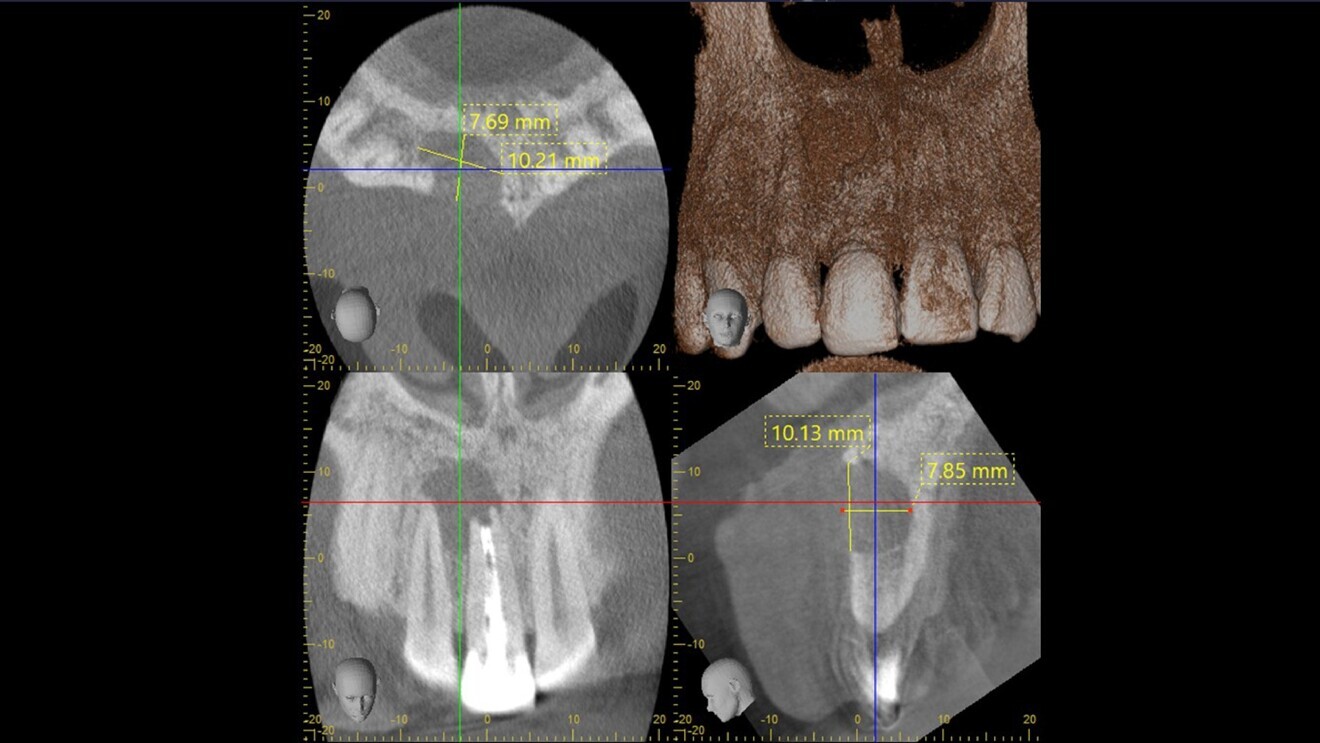

Fig. 4: CBCT scan showing the planned implant placement.

Typically, with such a large cyst, the treatment plan would be extraction, cyst enucleation and grafting, followed by implant placement after healing of the graft, and the patient would be provided with a provisional, often removable, prosthesis. However, I have for many years specialised in complex immediate implant placement and have published extensively on the use of low insertion torque with high success, even in the case of immediate provisionalisation. Accordingly, the risks and benefits were discussed with the patient, who elected for a simultaneous approach and immediate restoration. This was planned in the CBCT scan using i-Dixel software (Morita) for the placement of a PrimeTaper EV implant (Dentsply Sirona, 4.2 × 17.0 mm; Fig. 4), and a bovine bone mineral substitute was chosen as the grafting material.